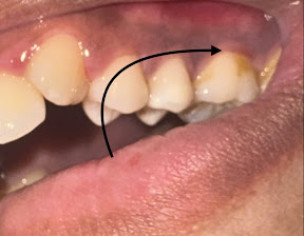

I have a constant itchy and inflamed sensation right here (MARKED BY THE ARROW). It’s very sensitive to cold and pressure, and I feel a throbbing pain here.

I’ve been chewing heavy mastic gum 3 times a day for 10 days to treat H. pylori. I think the heavy pressure may have impacted tartar or debris deep into my gum pockets.

I’ve had a tooth pulled before, and I’m very anxious about losing another one. Should I get the pocket depths checked and see if a deep cleaning (scaling) will resolve the inflammation?

looks lot of deposits,

calculus and might have cavity at the back side please contact or WhatsApp

Simple scaling n polishing will clean this along with all over